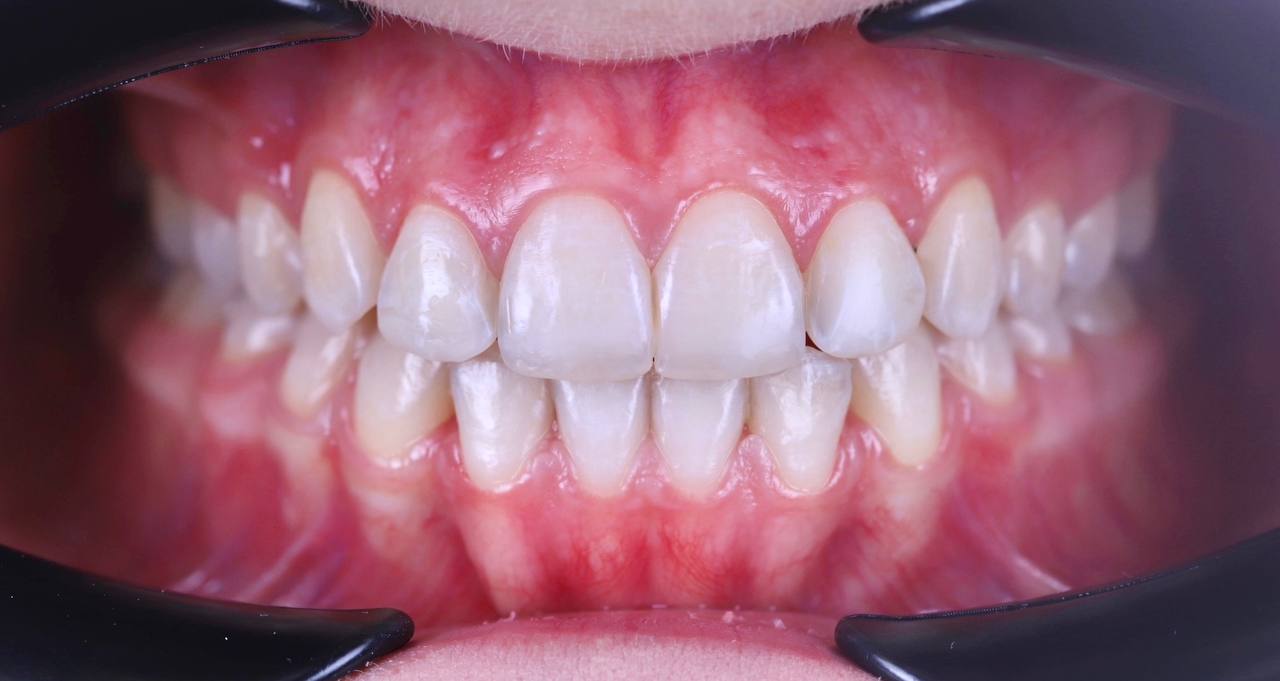

Я больше не стесняюсь улыбаться, моя улыбка стала белоснежной, яркой и неотразимой. Спасибо команде «Клиника ОК» за это Чудо!